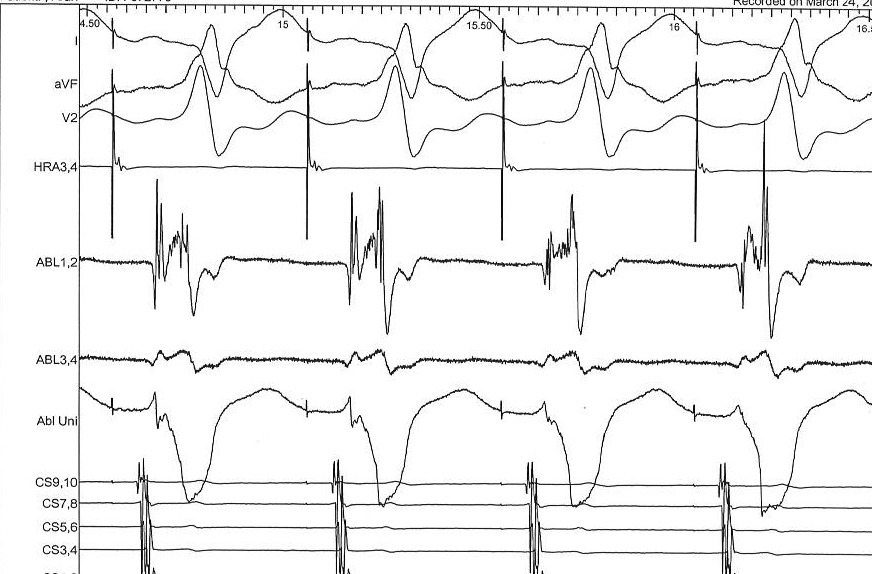

Ablation page

abl_page.jpg